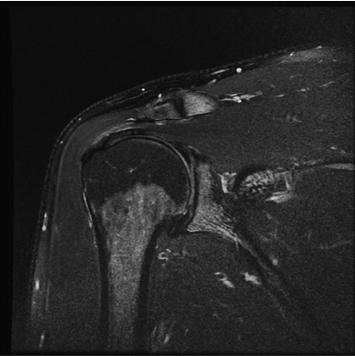

1:29 min촬영속도의 혁신, IAI

기존

IAI

IAI는 AI Deep learning을 통해 기존 장비의 촬영 프로토콜을 최적화합니다.

기존 프로토콜 대비 촬영 시간을 50% 단축시키며, 이미지 퀄리티는 증가합니다.